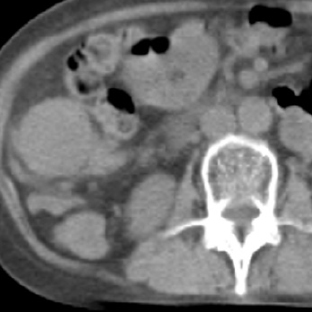

b. 単純CT

c. 123I-MIBG-SPECT/CT

図2 嚢胞変性した褐色細胞腫